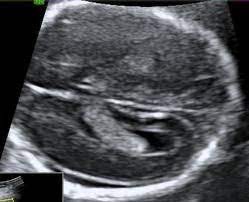

Prenatal Imaging Findings In Down Syndrome Practice Essentials Ultrasonography